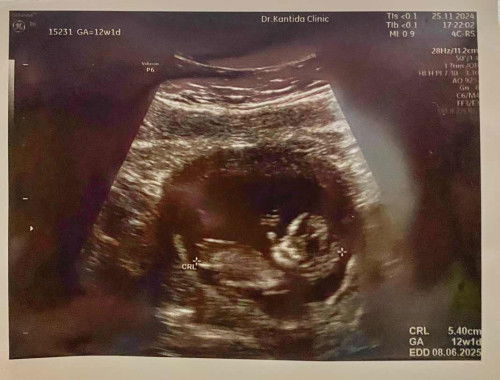

แชร์ประสบการณ์เลือดออกขณะตั้งครรภ์(ไตรมาสแรก) แต่ไม่ใช่ภาวะแท้งคุกคาม

มาแชร์ประสบการณ์เลือดออกขณะตั้งครรภ์ช่วง 6 วีคค่ะ เลือดออกครั้งแรกตอน 6 วีค ตื่นเช้ามามีเลือดสีแดงสดติดกางเกงนอนประมาณหนึ่งไม่มาก แต่แม่จิตตก ร้องไห้ รีบไปโรงพยาบาล ระหว่างรอตรวจ ก็สังเกตว่าเลือดออกไม่มากแล้ว แค่พอติดกางเกงในปนตกขาว คุณหมอซาวน์แบบผ่านช่องคลอดเผื่อเช็ค ปรากฏว่ายังมีเลือดค้างในช่องคลอด แต่น้องยังอยู่ เลยให้ยากันแท้งมา และห้ามเดินเยอะ ห้ามยกของหนัก แม่ทานยากันแท้งจนหมดประมาณ 2 วีค แต่สังเกตุดูก็ยังคงมีเลือดปนตกขาว ลักษณะสีน้ำตาล แต่ไม่ทุกวัน จึงแจ้งคุณหมอที่ฝากครรภ์ คุณหมอจะซาวน์เช็คให้ทุกครั้งที่ไปตรวจ น้องแข็งแรงดี โตตามเกณฑ์ คุณหมอจึงไม่ได้ให้ยามา แต่แม่ก็จะใช้ชีวิตอย่างระวังตัว และกังวลตลอดเวลา จน 10 กว่าวีค จนวันนึงบังเอิญไปเจอคลิปนึงใน ตต. มีอาการคล้ายกัน เจ้าของคลิปตรวจพบติ่งเนื้อบริเวรปากช่องคลอดซึ่งตัดออกเลือดก็หยุดไหล วันนัดตรวจช่วง 12 วีค เราจึงลองแจ้งหมอแบบที่เห็นในคลิป หมอจึงขอตรวจภายใน ปรากฏว่าเราตรวจเจอติ่งเนื้อขนาด 1 เซน หมอจึงให้ตัดออกและส่งชิ้นเนื้อไปตรวจ หลังตัดติ่งออกได้ 2 วันแม่ก็ไม่มีเลือดออกอีกเลยค่ะ ผลชิ้นเนื้อปกติไม่ร้ายแรง สาเหตุเนื่องจากฮอร์โมนเปลี่ยน ปากช่องคลอดขยาย ทำให้ติ่งเนื้อปลิ้นออกมา แค่ตัดออกเลือดก็หยุดค่ะ ตอนนี้เข้า 13 วีค ใช้ชีวิตปกติแล้ว หายกังวล น้องโตตามเกณฑ์ ผล nipt ออกแล้ว โครโมโซมครบ และน้องเป็นสาวน้อยค่ะ คุณแม่บ้านไหนมีอาการคล้ายๆกันลองสังเกตอาการดูนะคะ มีเลือดออกคล้ายๆตกขาวปนเลือดสีน้ำตาล แต่ไม่มีอาการปวดท้อง เผื่อจะมีอาการคล้ายๆกันค่ะ ขอให้คุณแม่ทุกคนตั้งครรภ์อย่างปลอดภัยจนถึงวันกำหนดคลอดนะคะ 😊😊